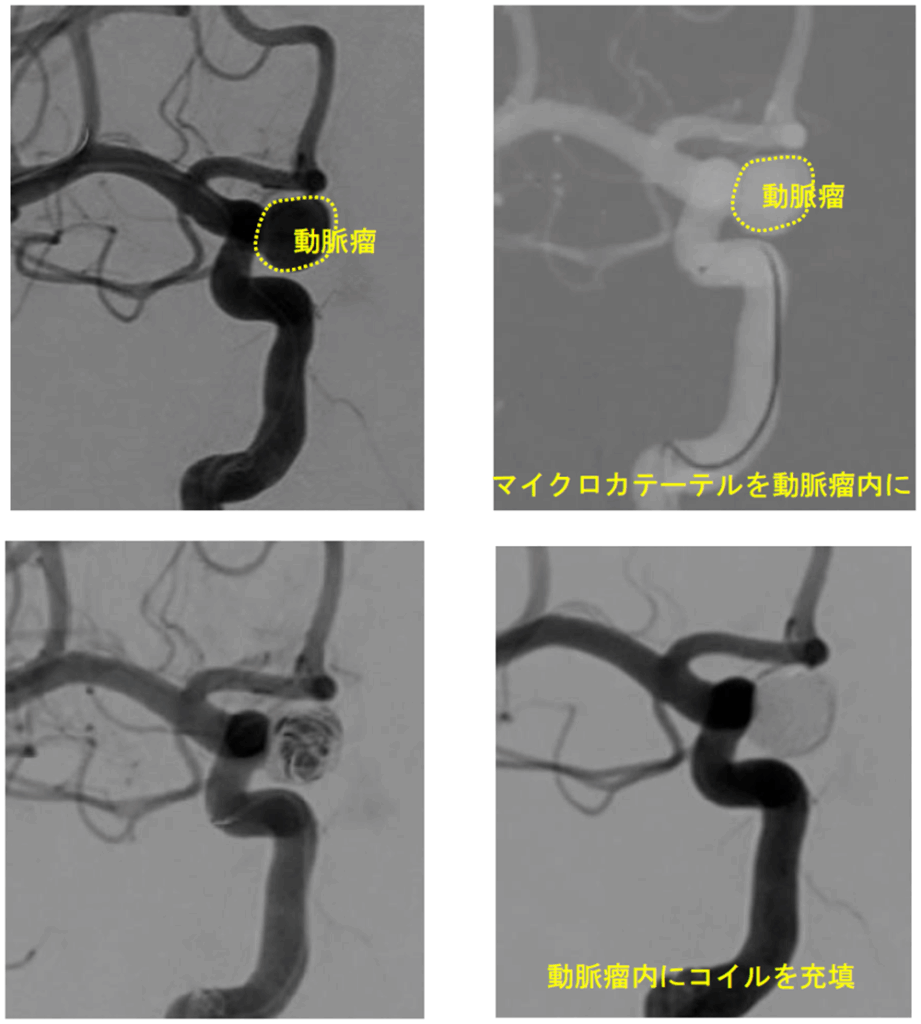

②脳血管内治療(カテーテル治療)

頭を開かず、足の付け根や手首の血管からカテーテルを挿入して行う低侵襲治療です。近年大きく進歩し、重要な治療選択肢となっています。

● コイル塞栓術

動脈瘤内にプラチナ製コイルを充填し、血流を遮断します。低侵襲で術後回復が比較的早い治療法です。